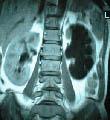

4.肾母细胞瘤(胚胎瘤) 注意发病年龄(大多发生在幼儿,偶见于中青年)及有无下述表现:①以腹部肿物为第一症状,贫血、低热、高血压常见,但血尿少见。②尿路造影不显影或显示肾盂、肾盏变形移位,肾影增大,肿瘤区可见钙化影,输尿管可被肿瘤推向中线。③放射性核素肾扫描,显示患肾放射性缺损及稀疏。④肺、骨骼可有早期转移。⑤B超、CT或MRI检查。

其中,B超是筛查肾癌最合适的方法之一,可发现直径08cm的肾肿瘤。如果B超发现异常者,应进行CT检查,该方法可发现05cm以上的肿瘤,仍不能确诊者还要进行核磁共振检查。